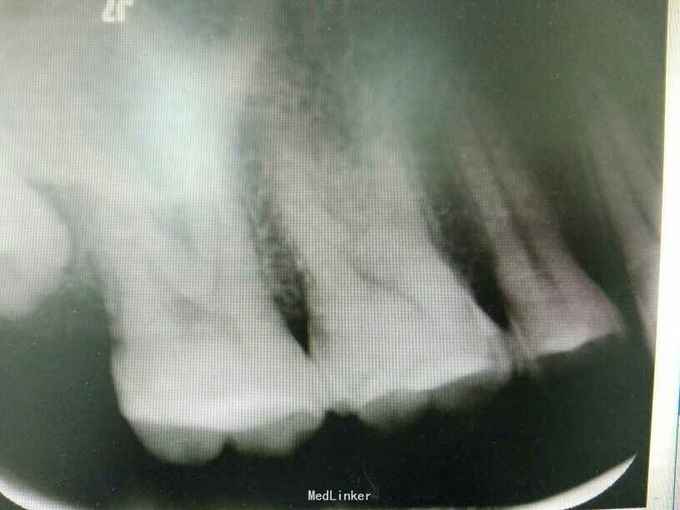

检查:17合面见牙色充填体,冷+,探-,叩不适,无松动,牙龈未见异常 x线:17冠方见高密度充填影像,近髓,近中根周膜略增宽 18低位阻生

诊断:17牙髓炎 治疗计划:17根管治疗术 处置:17开髓,揭顶,见少量渗出,探及MB、DB、P三个根管口,P疏通过程疼痛明显,干燥,置失活剂,氧化锌暂封 一周后复诊:主诉无不适,氧化锌暂封完整在位,去除氧化锌,清理髓腔,测量根管长度,MB=P=19mm,DB=21mm,根管锉扩大至MB、DB25#,P至35#,双氧水、生理盐水交替冲洗,干燥根管,髓腔置CP棉球,氧化锌暂封 一周后复诊:无不适,氧化锌暂封在位,去除暂封,试主尖,冷侧牙充填,根尖片显示:恰填。 一周后复诊:无不适,叩-,患者因经济原因拒绝修复治疗,去除暂封后,磷酸锌垫底,树脂充填,调合,磨光。